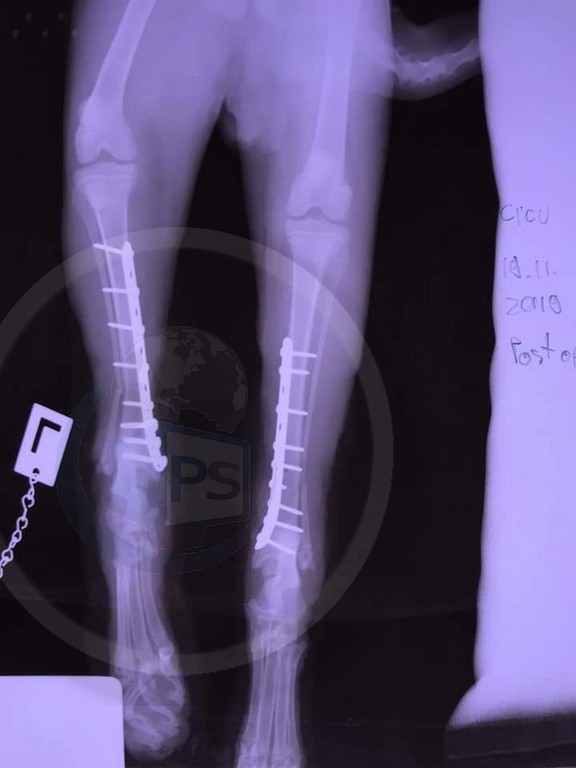

Așa am aflat, de exemplu, de povestea motanului Felix, care nu a avut nicio șansă de supraviețuire, potrivit medicilor. Motănelul a fost grav rănit după ce a fost lovit de o mașină, alegându-se cu fracturi la nivelul lăbuțelor, care i-au pus viața în pericol.

Totul se întâmpla în data de 18 noiembrie 2019. O femeie s-a încăpățânat să nu accepte verdictul medicilor veterinari, care au concluzionat că animalul trebuie eutanasiat, și a început o cursă contracronometru pentru a-i salva viața. În 19 noiembrie 2019 a apelat la un alt medic veterinar, care a făcut tot posibilul să îl salveze...și a reușit.

Săptămâna trecută am făcut ultima radiografie la piciorușul cu risc din care am aflat că piciorușul este salvat, osul s-a refăcut complet și nu mai pune semne de întrebare. Așa că Felix a fost salvat, i-au fost recuperate ambele piciorușe fracturate și are acum și o familie frumoasă care îl iubește enorm”.